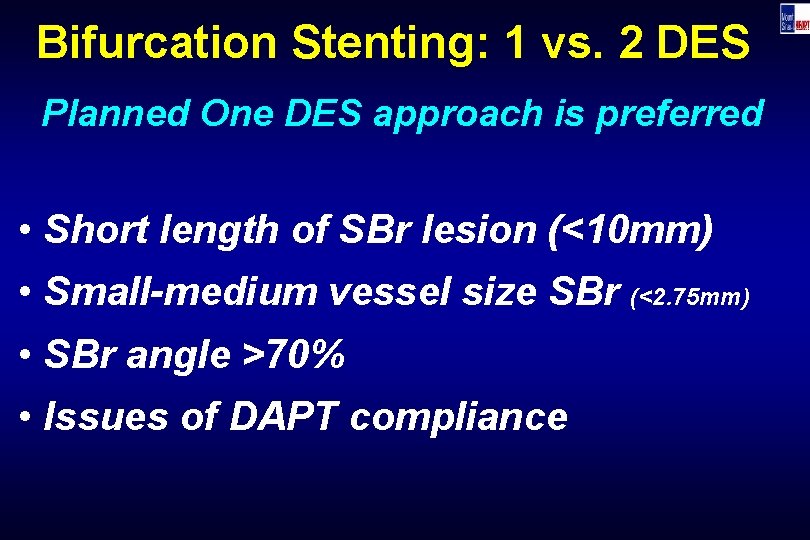

Bifurcation Stenting: 1 vs. 2 DES Planned One DES approach is preferred • Short length of SBr lesion (<10 mm) • Small-medium vessel size SBr (<2. 75 mm) • SBr angle >70% • Issues of DAPT compliance